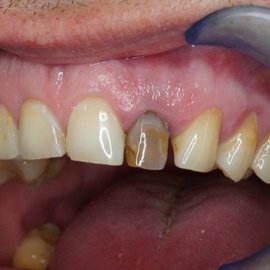

Wybielanie obejmujące pojedyncze zęby jest dość często spotykane. Najczęstszą przyczyną dyskoloracji zęba jest obumarcie miazgi i brak następowego poprawnego leczenia kanałowego, lub leczenie nieprawidłowe. Czasami udaje się przeprowadzić proces wybielania, który jest zadowalający dla pacjenta, a czasami w oparciu o uzyskany wynik można przeprowadzić leczenie protetyczne np. koroną lub licówką całoceramiczną.

Trzeba jednak uważać, ponieważ nieumiejętnie przeprowadzone wybielanie może być przyczyną resorpcji wewnętrznej i może sie skończyć utratą całego zęba...juz wybielonego. Poniżej zdjęcia przed i po leczeniu mikrochirurgicznym resorpcji.